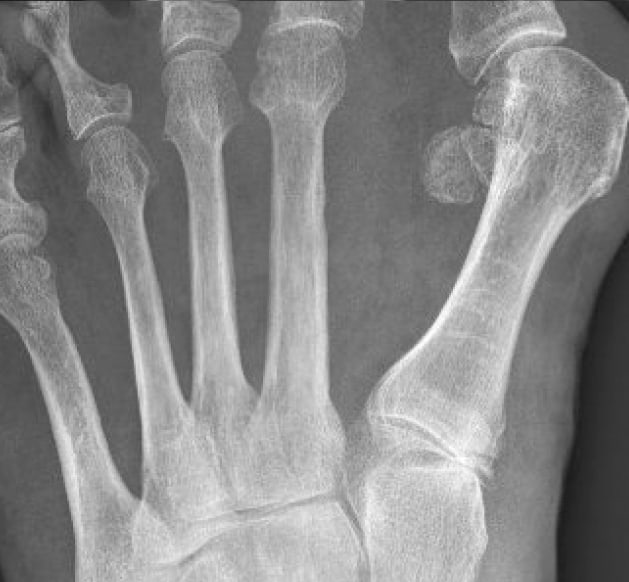

X-ray image preoperatively

Pronounced severe hallux valgus with metatarsus primus varus